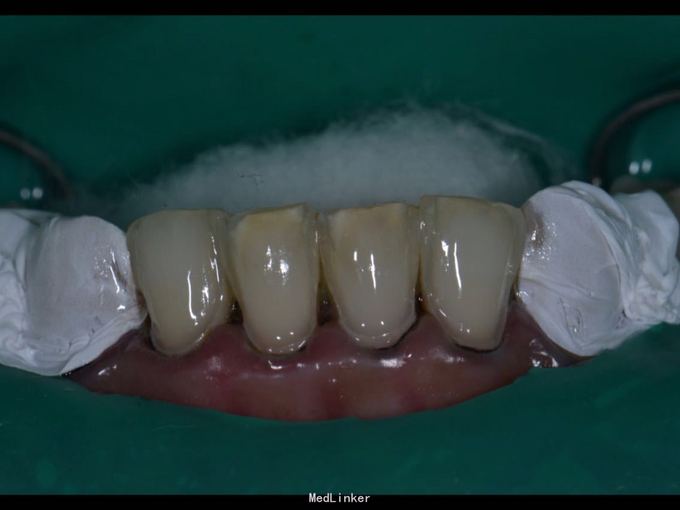

11 12 21 22死髓牙,不良修复体,牙龈炎 36 37 46 47残根 牙列不齐 处置:全口洁治。 比色,拍照,取模型做蜡型。 拆除旧修复体,拆桩核,做根管治疗,纤维桩修复,牙体预备,取模,做临时冠,粘固。11 12 21 22全瓷冠修复,13 14 23 24 31 32 33 34 41 42 43 44瓷贴面修复。

1.旧修复体覆合大,11 212 21 22龈缘位置较低且不对称,能做冠延长协调红白美学,更好 2.拆旧桩核要小心根折,用超声振动,一点一点拆.11桩核粘固比较牢固,根尖炎,定期观察行根尖手术倒充填。 3贴面的粘接,耐心